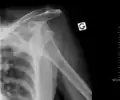

An anterior dislocation of the shoulder

Anterior dislocation of the right shoulder. AP X ray

Anterior dislocation of the right shoulder. Y view X ray.